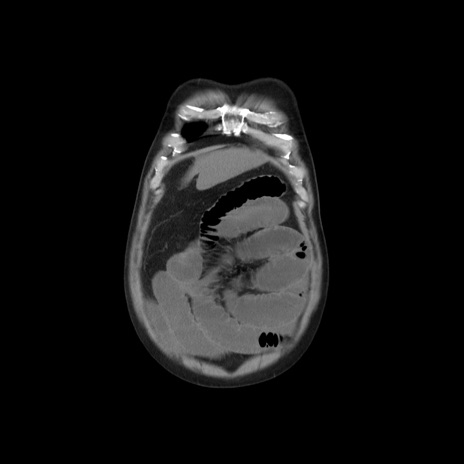

横断像

【症例】 60歳代男性

【主訴】 腹部膨満、嘔吐

【現病歴】5日前頃より倦怠感を認め食事量減少し4日前の朝嘔吐、食事摂取困難となった。 3日前近医受診し点滴施行され整腸剤などを処方された。 当日他院を受診し、腹部膨満著明、炎症反応の上昇(CRP10.8、WBC11200)あり、紹介受診となる。

【身体所見】 意識JCS1 受け答えがはっきりしないBP 111/57mHg、 P 67bpm、、BT35.2°C、SpO2 97%(RA)、 腹部:膨隆、打診で鼓音あり、全体的に圧痛有り、腸蠕動音(-)、反跳痛ははっきりせず。

【データ】WBC 11400、CRP 14.20